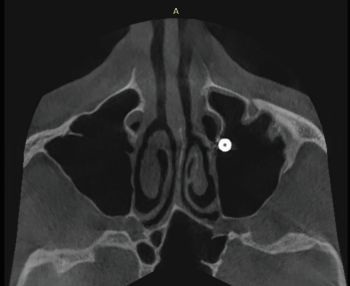

X-rays exams (i.e. OPG and CBCT) revealed the position of the displaced implant, which subsequently migrated near the ostiomeatal complex (OMC). It’s worth pointing out that immediately after their displacement, dental implants are usually located on the floor of the maxillary sinus or in the immediate vicinity; after a while, the displaced implants start to migrate against the gravitational force in the direction of the maxillary sinus ostium (as reported in the present clinical case) thanks to the strong mucociliary clearance by the sinus mucosa as well as nasal and intrasinus pressure changes. Notably, no reactive changes of the sinus membrane were observed (Figs. 1–5).

Fig. 4: Pre-op CBCT radiographic exam (axial section)